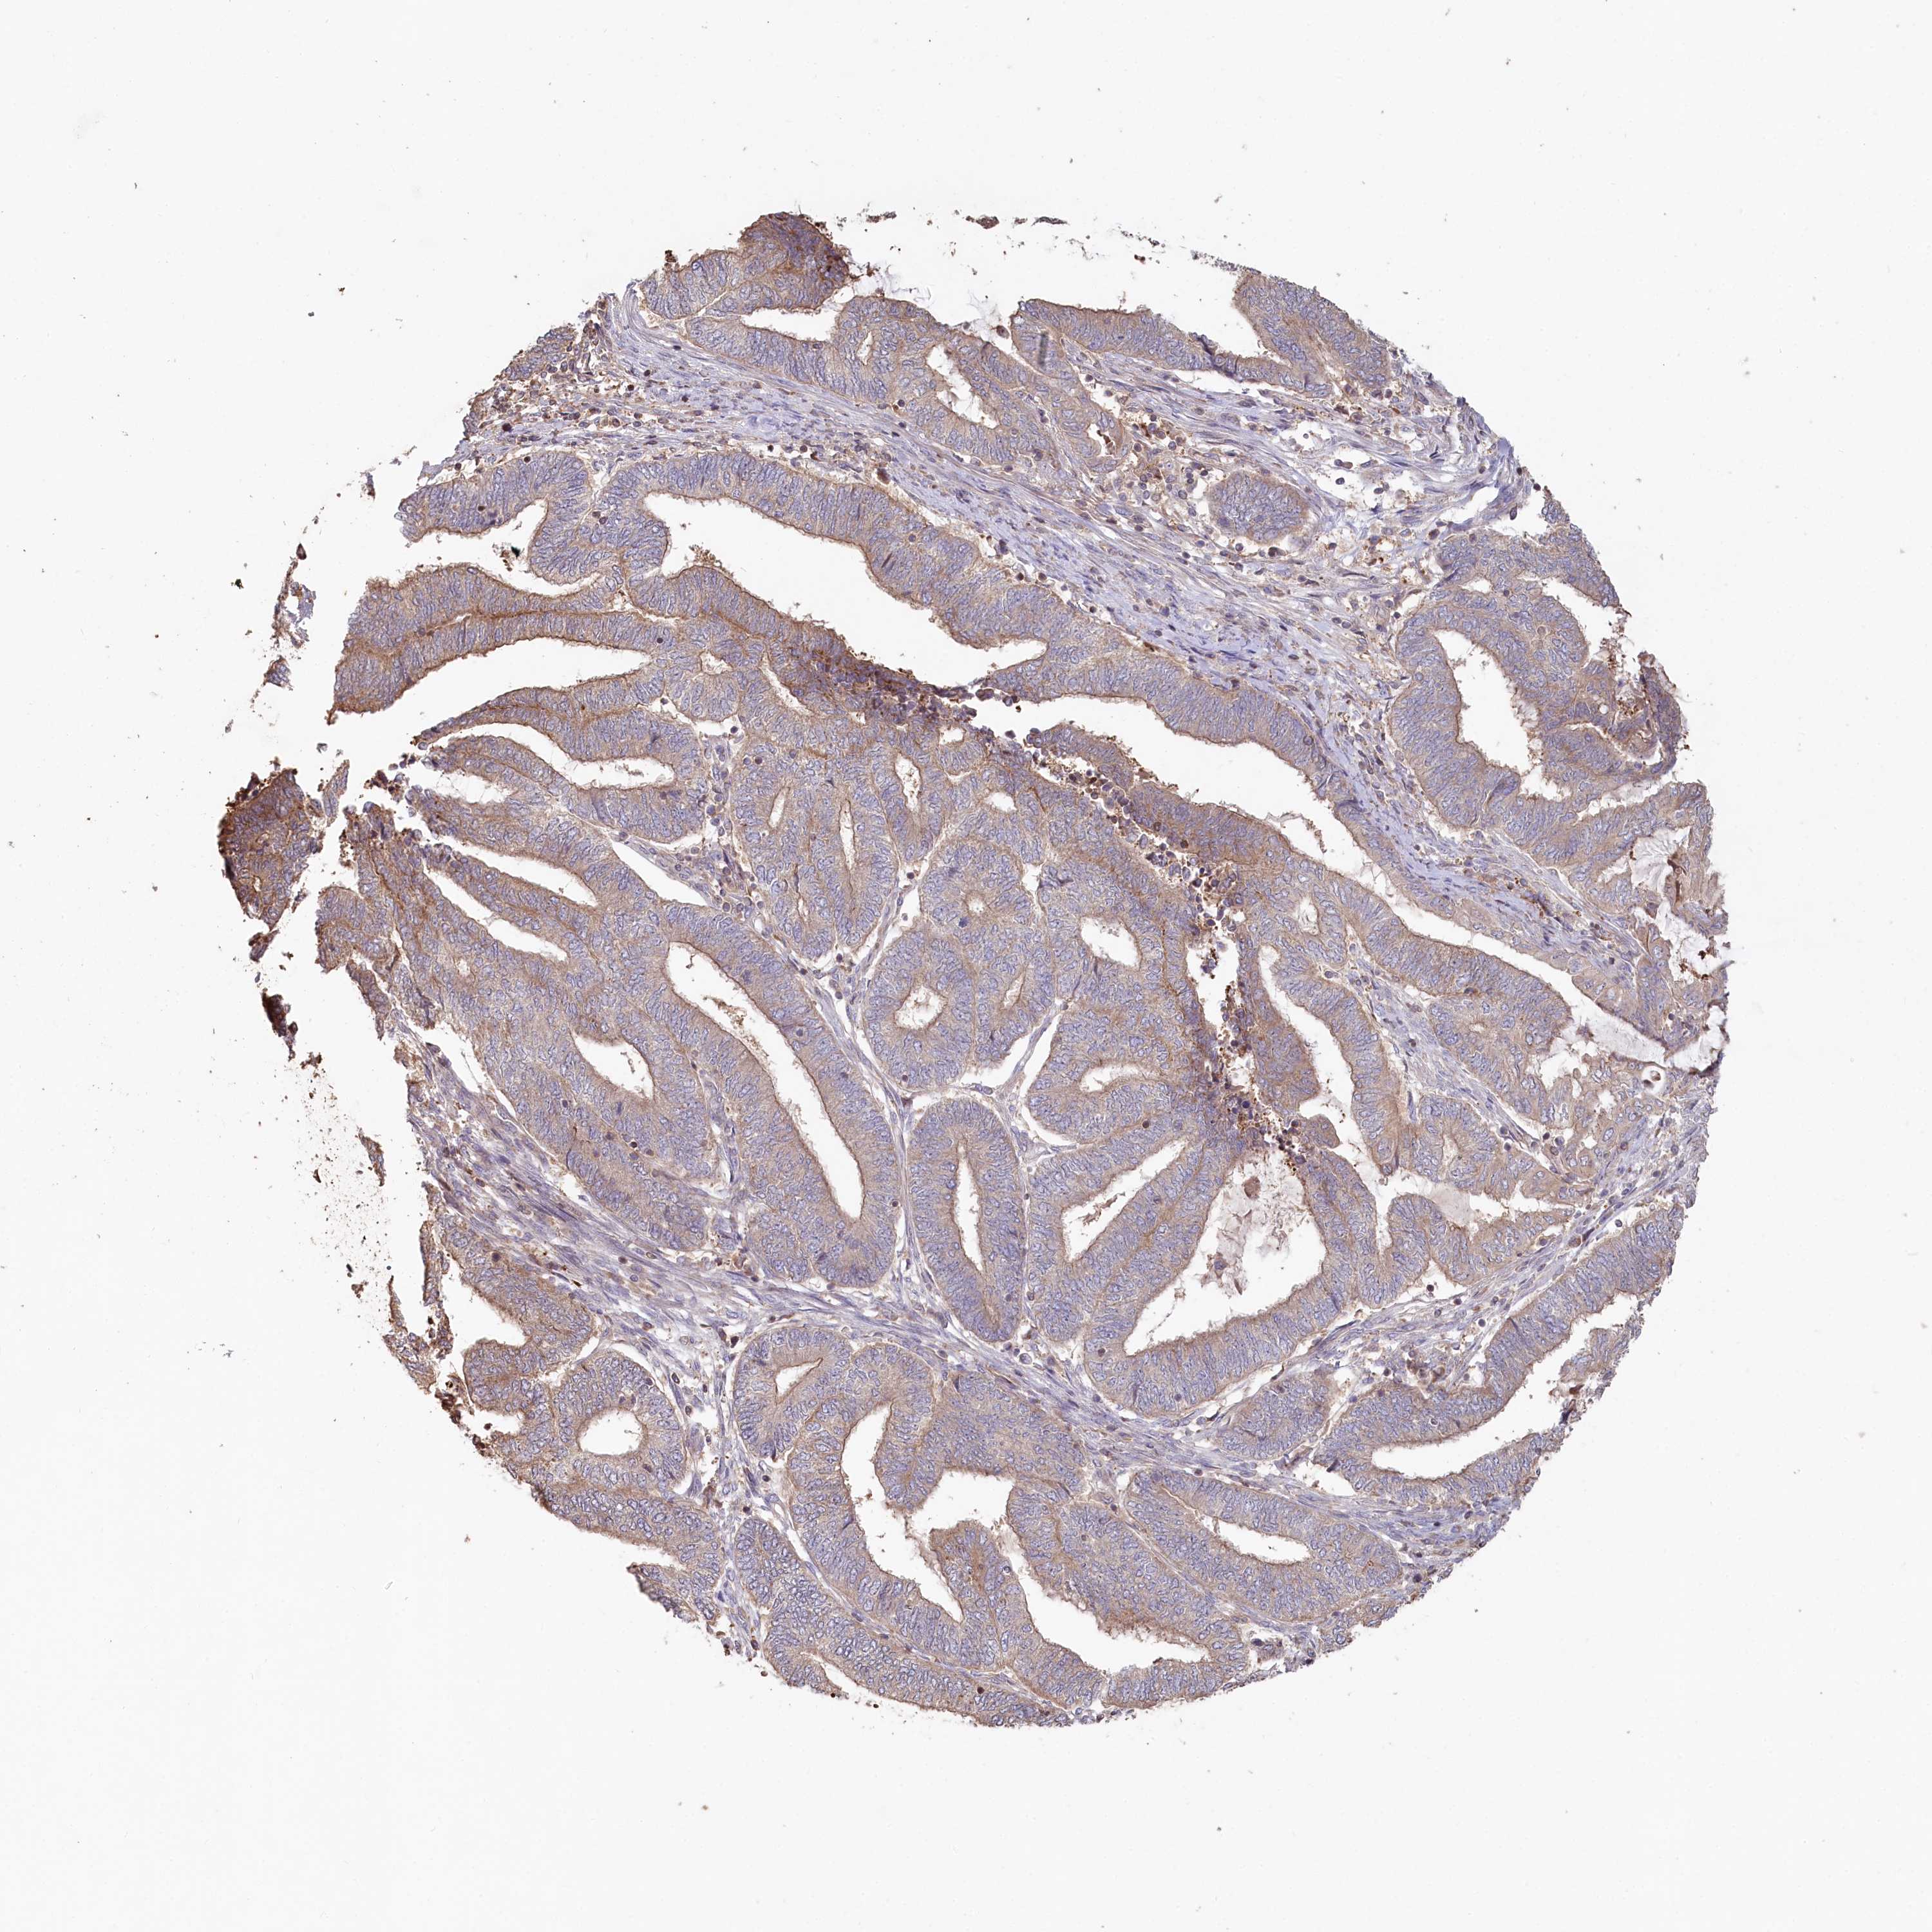

ENDOMETRIAL CANCER - Protein expressioni

A mouse-over function shows sample information and annotation data. Click on an image to view it in a full screen mode. Samples can be filtered based on level of antibody staining by selecting one or several of the following categories: high, medium, low and not detected. The assay and annotation is described here.

Note that samples used for immunohistochemistry by the Human Protein Atlas do not correspond to samples in the TCGA dataset.

Antibody stainingi

Antibody staining in the annotated cell types in the current human tissue is reported as not detected, low, medium, or high, based on conventional immunohistochemistry profiling in selected tissues. This score is based on the combination of the staining intensity and fraction of stained cells.

Each image is clickable and will lead to virtual microscopy that enables deeper exploration of all samples and also displays staining intensity scores, fraction scores and subcellular localization as well as patient and tissue information for each sample.

Antibody HPA038547

Antibody HPA038548

Staining

High

Medium

Low

Not detected

Intensity

Strong

Moderate

Weak

Negative

Quantity

>75%

75%-25%

<25%

None

Location

Nuclear

Cytoplasmic/membranous

Cytoplasmic/membranous,nuclear

Adenocarcinoma, NOS